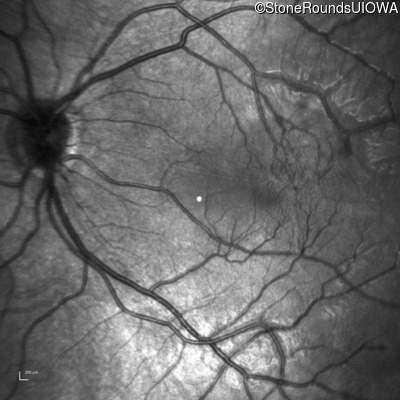

Infrared Fundus Photograph - Left - 20/80

Exemplar